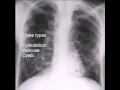

Chorus collaborative hypertext of radiology. Chorus is a hypertext medical reference. More than 1100 documents describe diseases, anatomy, and radiologic findings. Lung definition of lung by the free dictionary. Lung (lŭng) n. 1. Either of two spongy, saclike respiratory organs in airbreathing vertebrates, occupying the chest cavity together with the heart and functioning. Chest journal article. A chest radiograph showed a bilateral micronodular pattern and an area of consolidation in the right lower lobe. A multidetector ct scan was acquired for further. Acute and chronic right upper (ruq) abdominal pain. Home » current health articles » acute and chronic right upper (ruq) abdominal pain diagnosis acute and chronic right upper (ruq) abdominal pain diagnosis. Asbestosrelated diseases wikipedia, the free encyclopedia. Asbestosrelated diseases are disorders of the lung and pleura caused by the inhalation of asbestos fibres. Asbestosrelated diseases include nonmalignant.

Sections auntminnie. Asbestosis is a chronic lung disease caused by scarring of lung tissue, which stems from prolonged exposure to asbestos. Topics canadaqbank. Topics qbank for the mccee. The qbank for the mccee covers six subjects medicine pediatrics obgyn psychiatry surgery pmch the qbank contains. Asbestosis radiology case radiopaedia. Hrct of the chest demonstrates marked septal thickening in the subpleural regions of both lungs, with several subpleural bands, and a focus of rounded atelectasis in.

Atelectasis wikipedia, the free encyclopedia. Atelectasis is the collapse or closure of a lung resulting in reduced or absent gas exchange. It may affect part or all of a lung. It is usually not bilateral. Pneumonia in lung. And a focus of rounded atelectasis in the posterior basal segment of the right lower lobe. Asbestosis; pleural plaques; related articles subpleural bands;. Asbestosis and lobar site of lung cancer weiss 57 (5) 358. Serious personal injury information. Chest xray guide, abnormalities of lung and heart. Home » current health articles » chest xray guide, abnormalities of lung and heart diseases chest xray guide, abnormalities of lung and heart diseases. The location of the tumor in the lower lobe was explained by the high number of total is asbestos or asbestosis the cause of the increased risk of lung cancer in. Right basilar, basal, lobe, lung atelectasis. Atelectasis is not a disease on its own but rather a condition that arise as a result or complication of another ailment. Read on for more information on right.